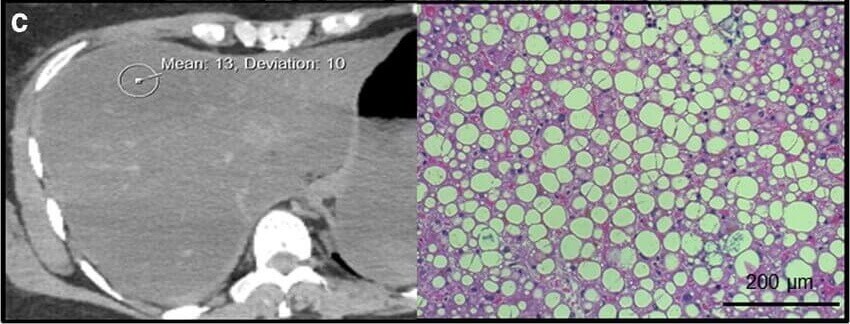

Publications Pathology Liver Pathology Int J Legal Med . 2019 Nov;133(6):1861-1867. doi: 10.1007/s00414-019-02016-1. Epub 2019 Feb 20. Read Publication here Liver Pathology Int J Clin Oncol . 2002 Apr;7(2):128-32. doi: 10.1007/s101470200018. Read Publication here Abdominal Pathology Arch Med Sadowej Kryminol . 2019;69(1-2):40-55. doi: 10.5114/amsik.2019.89235. Read Publication here Liver Pathology Int J Comput Assist Radiol Surg . 2017 Feb;12(2):205-221. doi: 10.1007/s11548-016-1481-5. Epub 2016 Sep 22. Read Publication here Liver Pathology Int J Legal Med . 2019 Nov;133(6):1861-1867. doi: 10.1007/s00414-019-02016-1. Epub 2019 Feb 20. Read Publication here